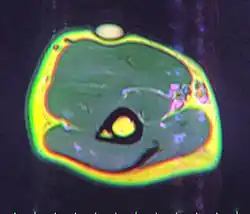

MRI showing lipoma of the arm -